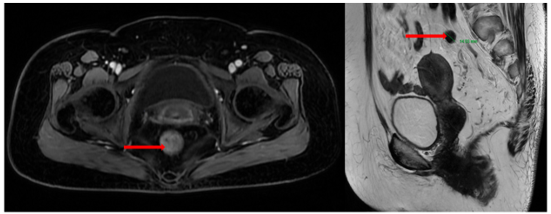

Nội soi đại–trực tràng (07/2024):

Ghi nhận hai tổn thương u sùi ở trực tràng, cách rìa hậu môn khoảng 5 cm và khoảng 10 cm. Tổn thương “phía trong” chiếm gần hết lòng trực tràng; tổn thương “phía ngoài” kích thước khoảng 3,0 cm. Ống hậu môn có đám tổn thương gồ ghề loang lổ.

Hình 1: Tổn thương u sùi ở trực tràng

Hình 2: Tổn thương gồ ghề loang lổ ở ống hậu môn

Giải phẫu bệnh (sinh thiết):

-         Trực tràng: ung thư biểu mô tuyến biệt hóa vừa.

-         Hậu môn: u tuyến ống, loạn sản độ thấp (tubular adenoma, low-grade dysplasia).